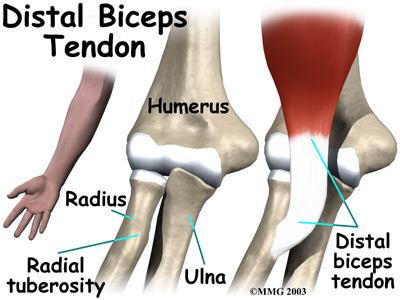

The lower biceps tendon is called the distal biceps tendon. The word distal means that the tendon is further down the arm. The upper two tendons of the biceps are called the proximal biceps tendons, because they are closer to the top of the arm.

The attaches to a small bump on the radius bone of the forearm. This small bony bump is called the radial tuberosity. The radius is the smaller of the two bones between the elbow and the wrist that make up the forearm. The radius goes from the outside edge of the elbow to the thumb side of the wrist. It parallels the larger bone of the forearm, the ulna. The ulna goes from the inside edge of the elbow to the wrist.

Not having surgery often results in significant loss of strength. Flexion of the elbow is somewhat affected, but supination (which is the motion of twisting the forearm, such as when you use a screwdriver) can be very affected. A distal biceps rupture that is not repaired reduces supination strength by about 50 percent.